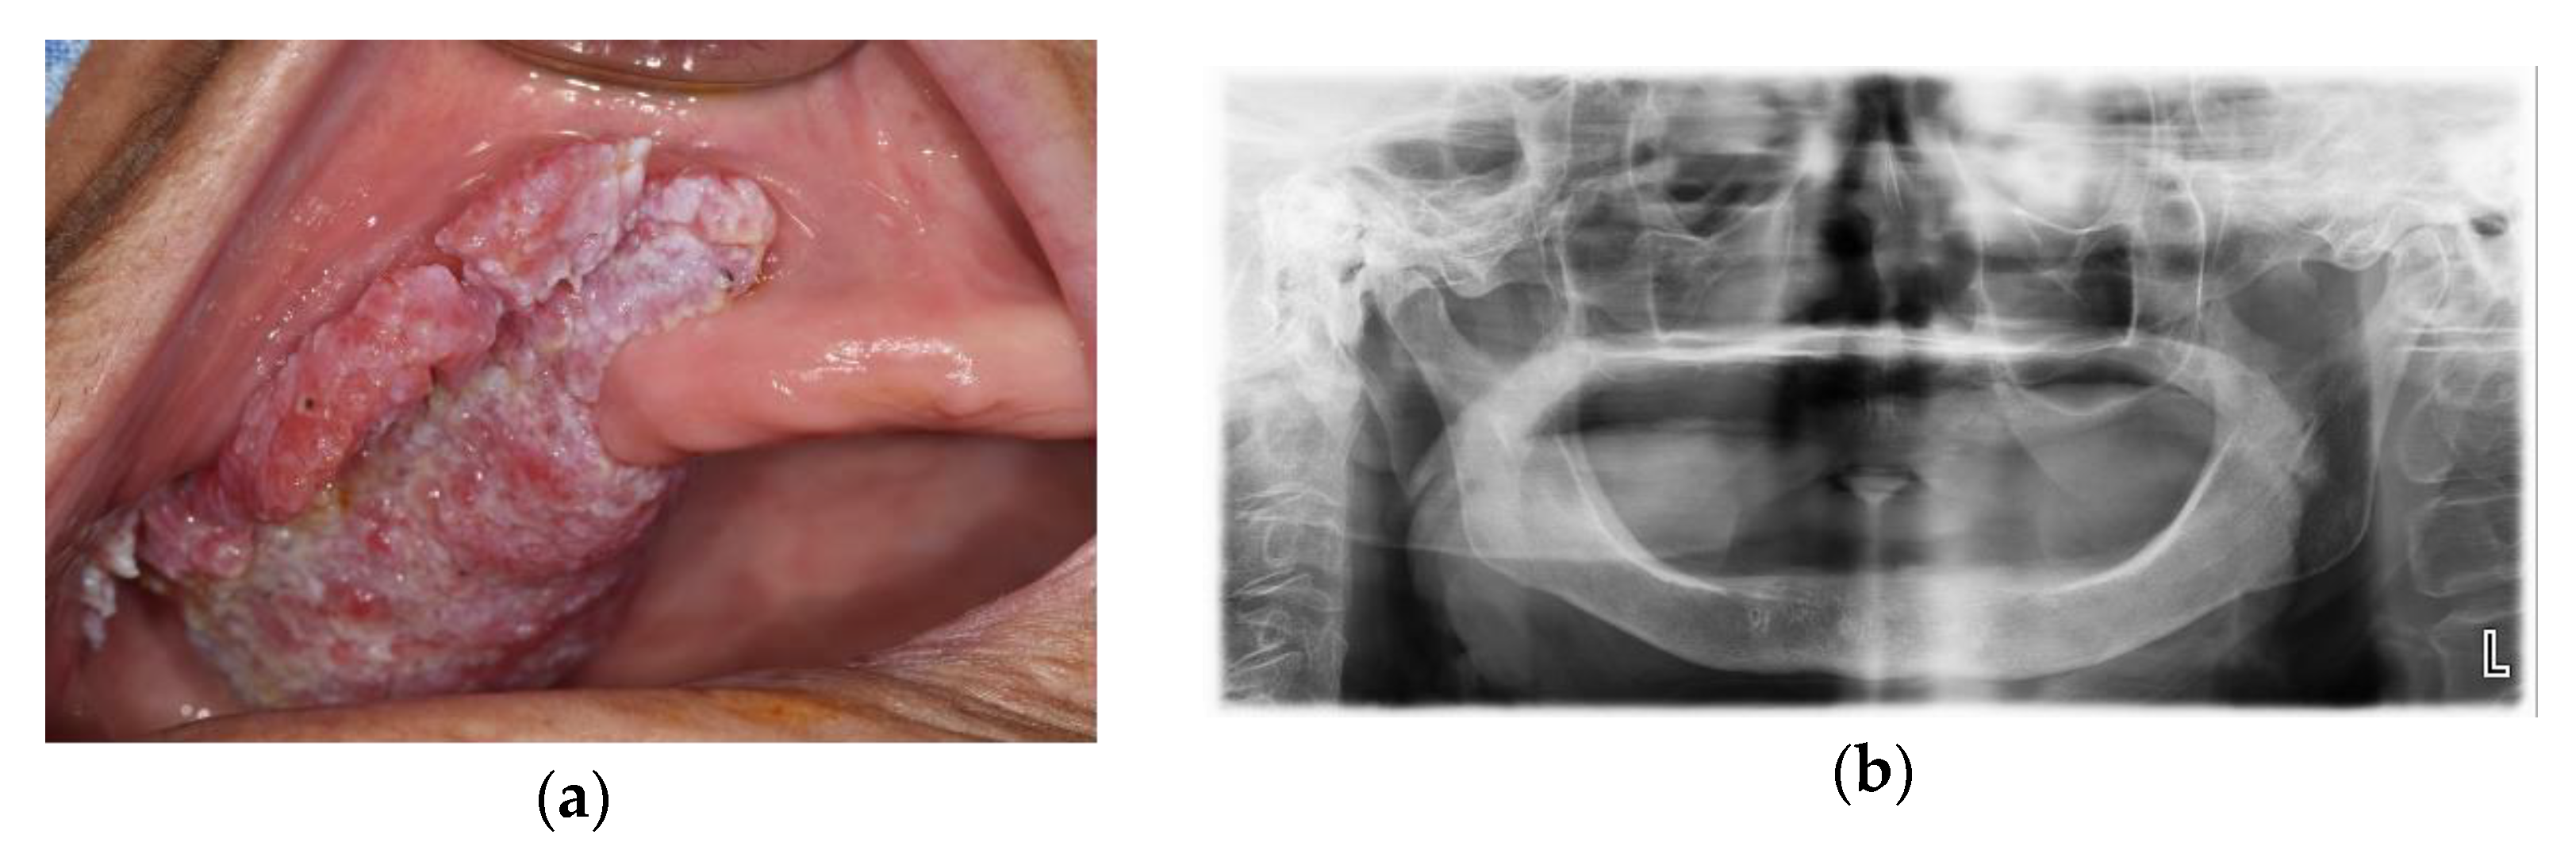

2.1. Case 1: SCC on Right Mandibular Buccal Mucosa

2.3. Case 3: Verrucous Carcinoma on Right Upper Gingiva